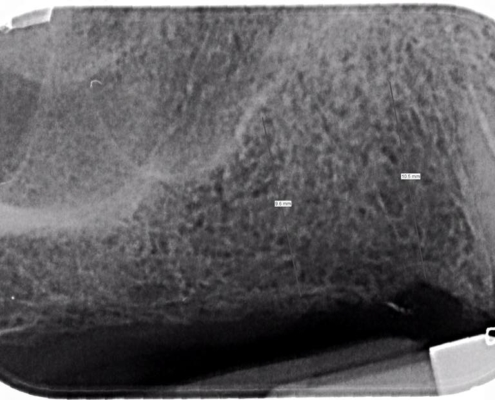

In seguito ad un trauma in piscina la bambina di 11 anni riporta la frattura del dente centrale superiore, le cure si susseguono affinché il dente si possa mantenere. La bambina attraverso l’ortodonzia estrusiva e la chirurgia in fase finale, un trattamento endodontico ed una protesi fissa in metallo ceramica le hanno permesso di mantenere la corona fino all’età di 18 anni, momento in cui la radice si è fratturata verticalmente sancendo l’estrazione della radice.